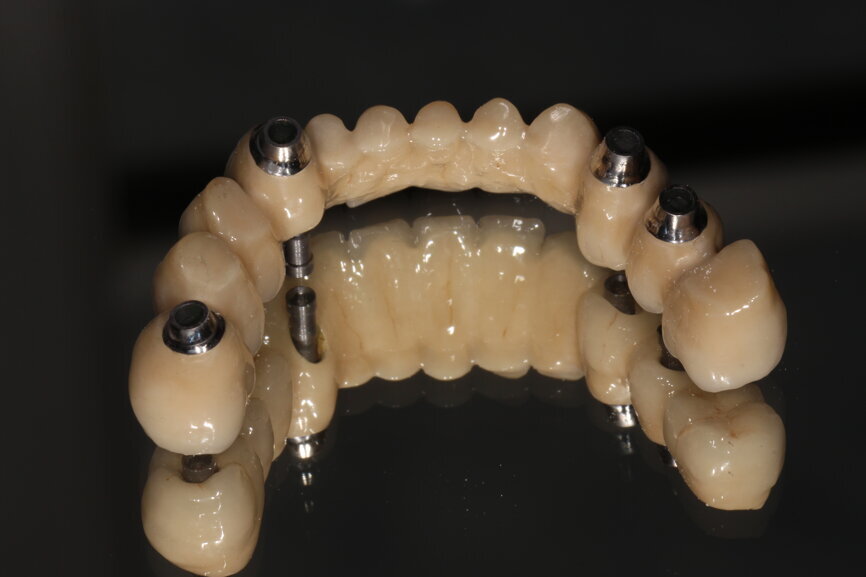

Fig. 12: Crowns on printed model.

Fig. 16: Createch framework fit surface.

Fig. 17: Finished screw-retained bridge in situ.